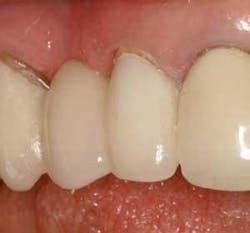

Figure 21 - Three-week postop view, facial closeup. Note the papilla development and soft-tissue architecture at three weeks postop. The implant-abutment-crown unit has integrated nicely.

Although only three-week postop results have been documented, already the technique holds promise. Papilla formation has occurred and the implant-crown unit is stable and healthy so far. The patient is taking more personal pride in her restoration and in her appearance, as evidenced by a dramatic improvement in plaque removal and overall oral hygiene observed at her three-week checkup.